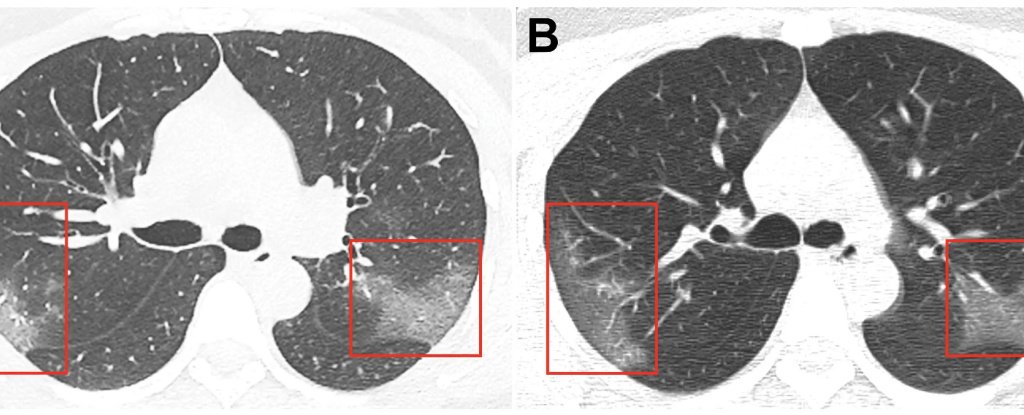

The long term lung damage for younger people definitely has me concerned. Almost everything I love doing requires healthy lungs.